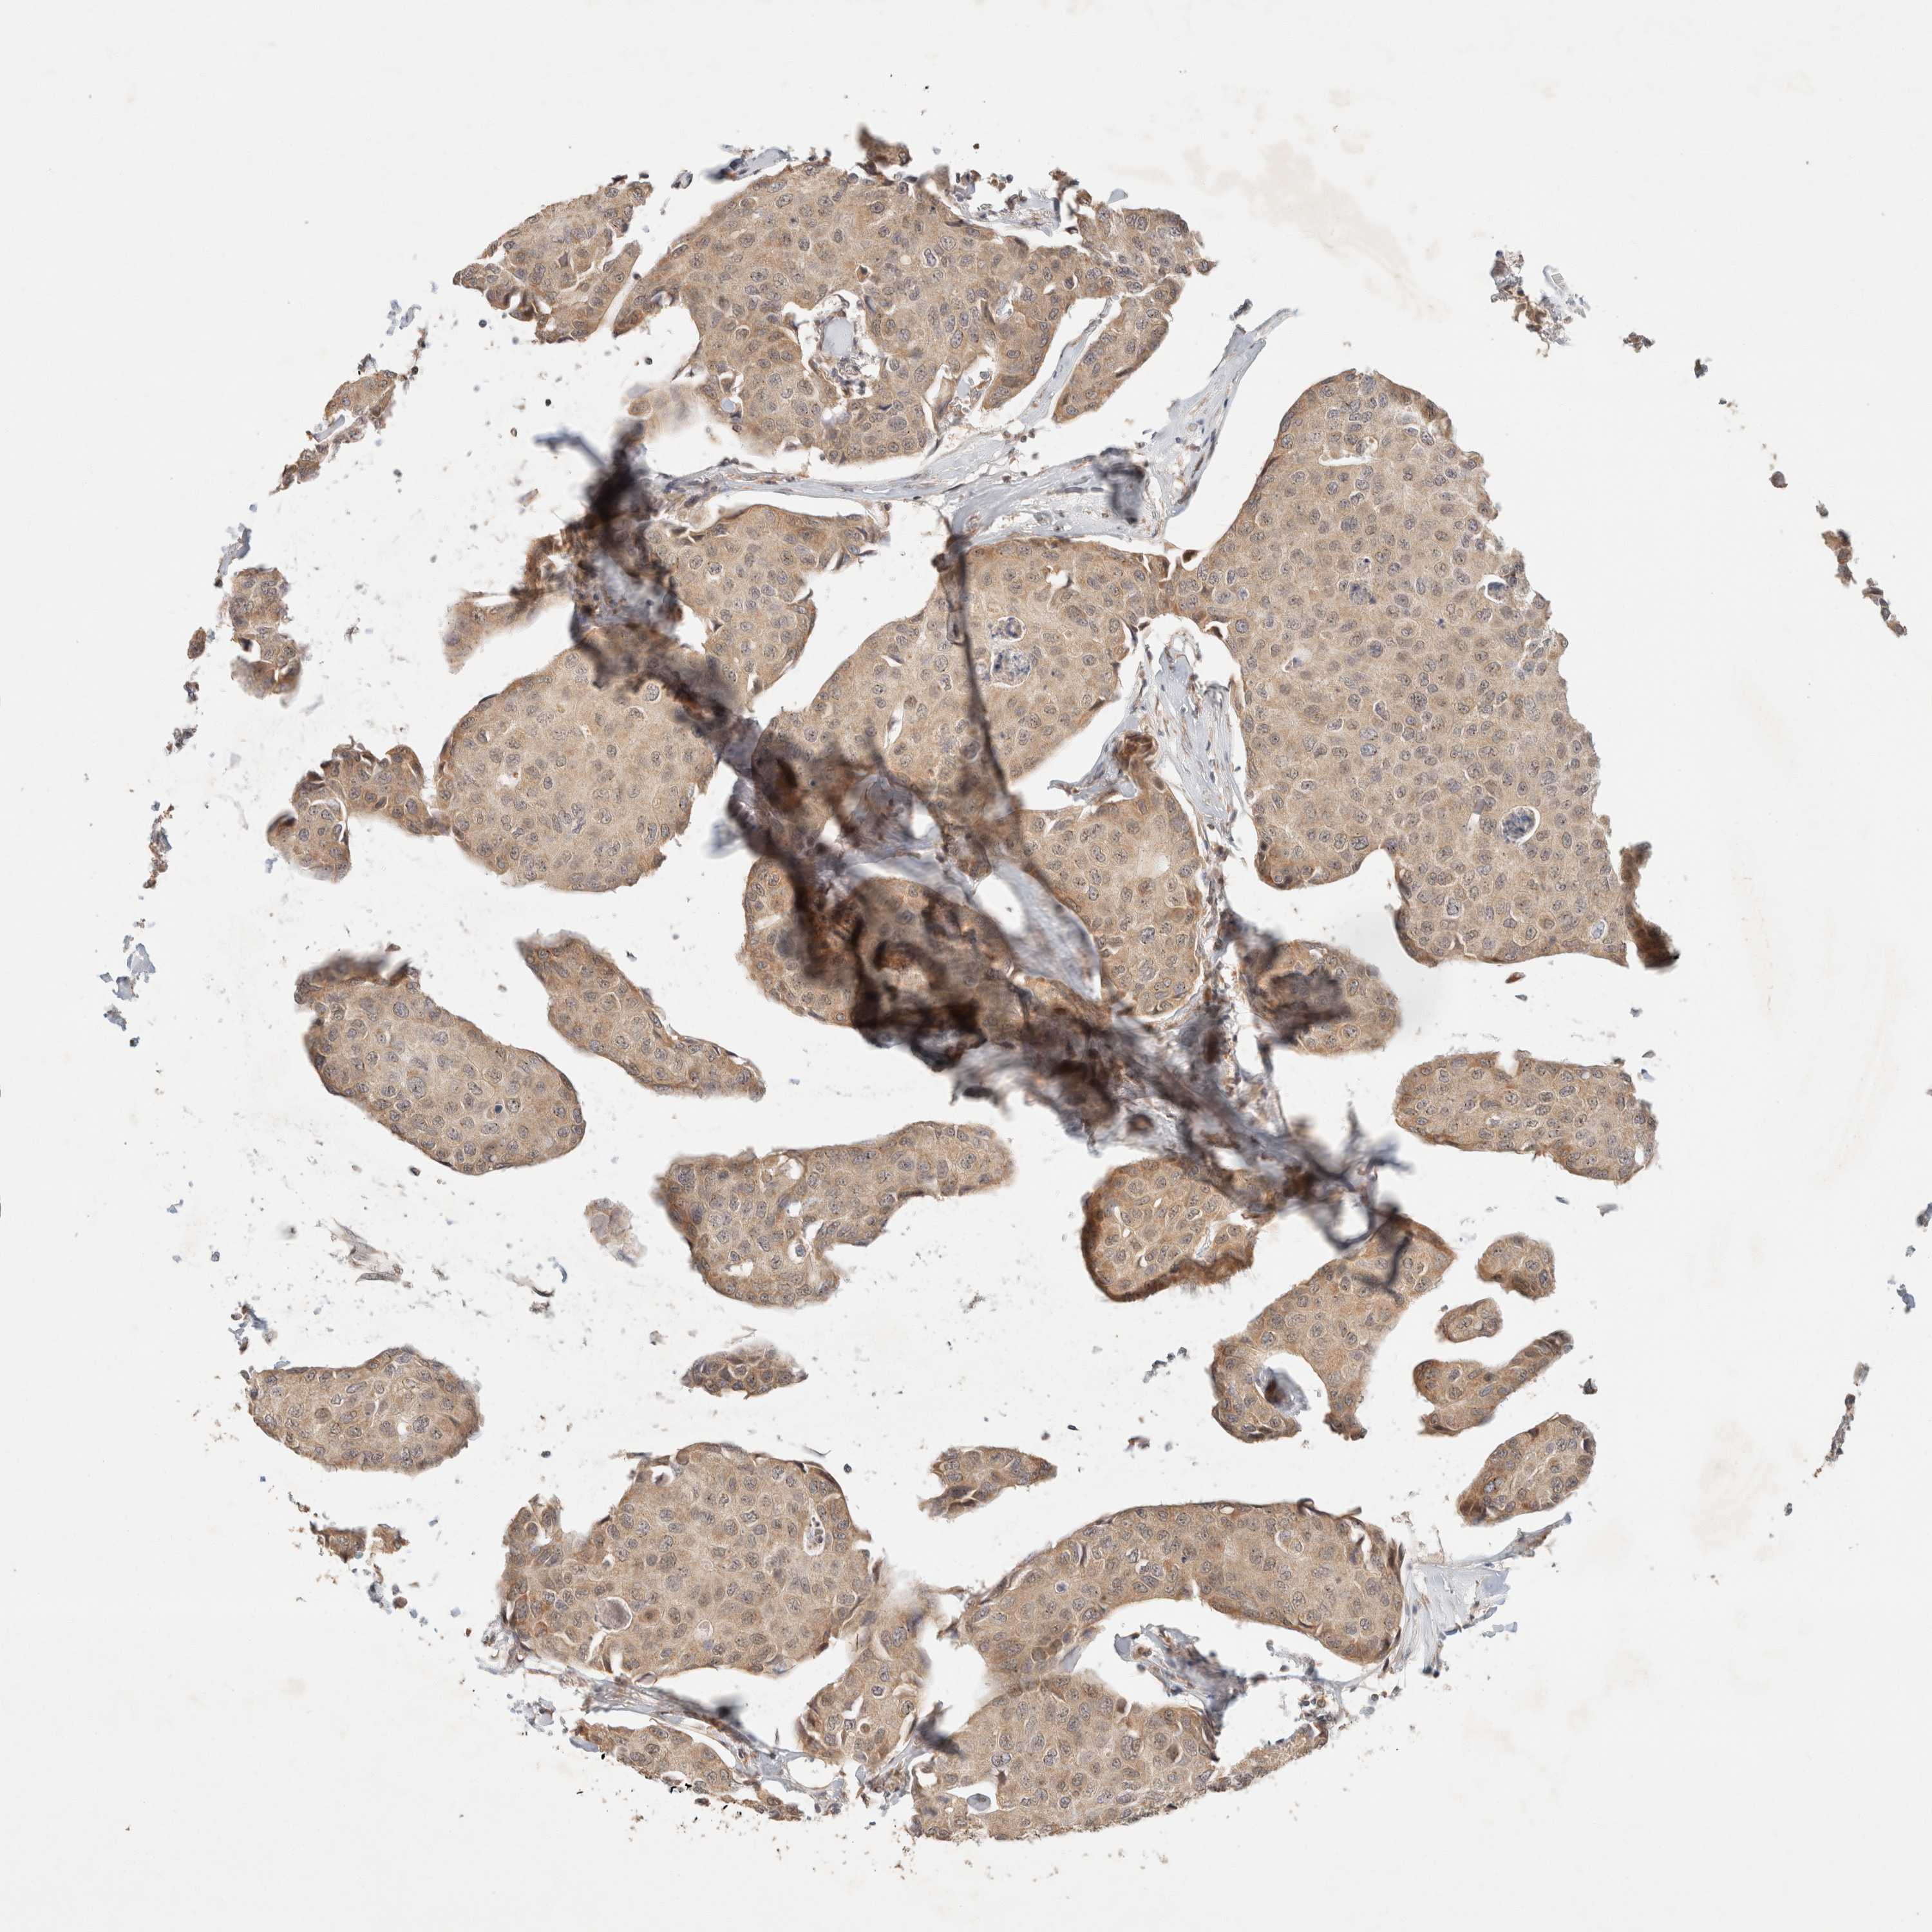

BRCA TCGA BRCA VALIDATION PROTEIN EXPRESSION